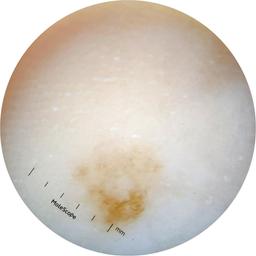

ISIC_2631400

MEL-SELF Trial, https://www.sydney.edu.au/medicine-health/our-research/research-centres/melself-project.html

Clinical

Field Value

acquisition_day 146

age_approx 70

anatom_site_1 Lower extremity

anatom_site_general lower extremity

concomitant_biopsy False

diagnosis_1 Benign

diagnosis_confirm_type single image expert consensus

family_hx_mm True

fitzpatrick_skin_type I

image_manipulation instrument only

image_type dermoscopic

lesion_id IL_2672529

patient_id IP_8223109

personal_hx_mm True

sex female